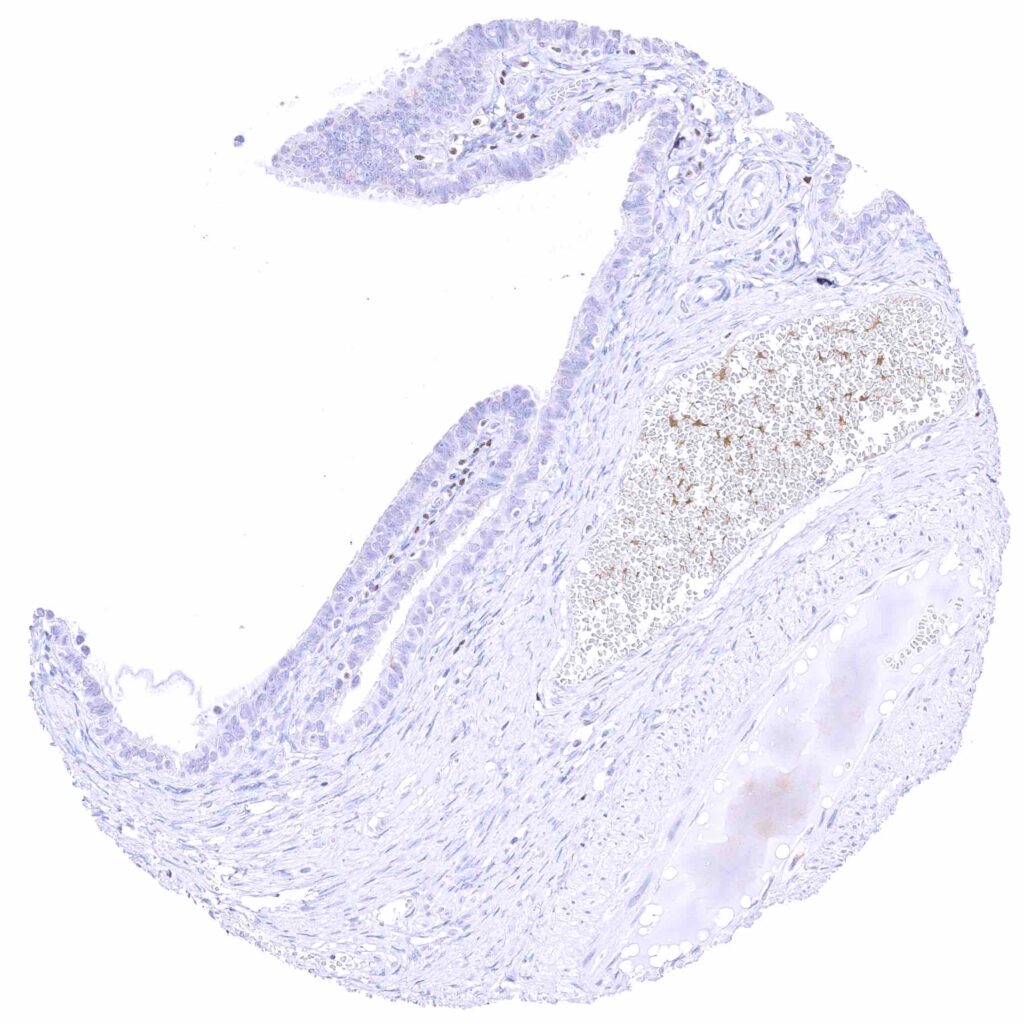

Prostate – Weak to moderate, nuclear GATA3 staining of basal cells. .jpeg

Epididymis (Caput) – Moderate to strong, nuclear GATA3 immunostaining of tall columnar cells nd of basal cells.

Seminal vesicle – Moderate to strong nuclear GATA3 positivity of epithelial cells.